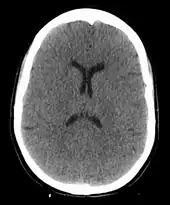

Anoxic brain injury following a hanging. The loss of grey white matter differentiation and small ventricles due to brain swelling are visible.

A hanging may induce one or more of the following medical conditions, some leading to death:

The cause of death in hanging depends on the conditions related to the event. When the body is released from a relatively high position, the major cause of death is severe trauma to the upper cervical spine. The injuries produced are highly variable. One study showed that only a small minority of a series of judicial hangings produced fractures to the cervical spine (6 out of 34 cases studied), with half of these fractures (3 out of 34) being the classic "hangman's fracture" (bilateral fractures of the pars interarticularis of the C2 vertebra).[26] The location of the knot of the hanging rope is a major factor in determining the mechanics of cervical spine injury, with a submental knot (hangman's knot under the chin) being the only location capable of producing the sudden, straightforward hyperextension injury that causes the classic "hangman's fracture".